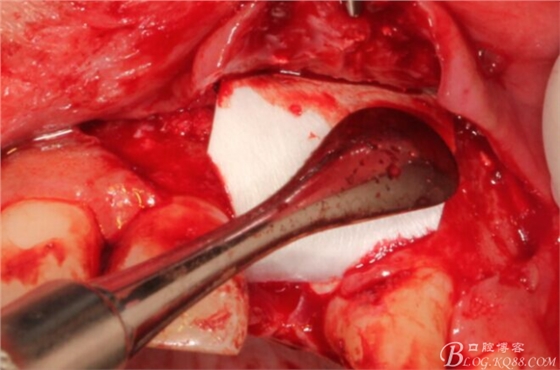

于是我果斷告知患者,手術(shù)失敗了,不能拖延,如不及時(shí)處理,炎癥繼續(xù)發(fā)展會(huì)很快波及鄰牙牙槽骨。患者接受我的建議。切開翻瓣,骨粉及生物膜消失了,骨吸收嚴(yán)重,幸運(yùn)的是,因?yàn)樘幚砑皶r(shí),鄰牙骨支持依然存在。

徹底掻刮。